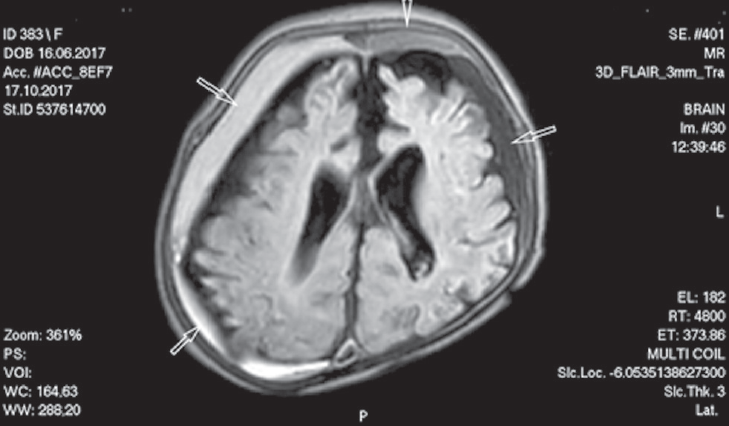

Субдуральная гематома — достаточно редкая, но серьезная патология головного мозга у детей грудного возраста, которая может привести к тяжелому неврологическому дефициту или закончиться летально. Субдуральные гематомы выявляются у 20–25 на 100 000 детей до 1 года. Ретроспективный анализ аутопсийного материала выявил, что у 72 % погибших детей в возрасте до 5 месяцев от внутричерепных кровоизлияний диагностированы субдуральные гематомы. По локализации субдуральные гематомы делятся на супра- и субтенториальные, преимущественно выявляются сочетанной локализации, которые лоцируются вдоль намета мозжечка и серпа головного мозга. Основной механизм развития субдуральных гематом связан с разрывом мостовых вен субдурального пространства в результате их натяжения, как травматической этиологии, так и возникающих при нетравматических повреждениях головного мозга, сопровождающихся прогрессирующей церебральной атрофией. Полагают, что одним из ведущих этиологических факторов развившихся субдуральных гематом у детей раннего возраста является перинатальное гипоксически-ишемическое повреждение головного мозга. Кроме того, формирование субдуральных гематом у детей раннего возраста может наблюдаться при внутриамниотических инфекциях, врожденных ферментопатиях и прежде всего у детей с ацидоуриями. У некоторых детей грудного возраста субдуральные гематомы протекают без клинической манифестации, но в большинстве случаев сопровождаются развитием неврологических нарушений, как в острый, так и в отдаленный периоды. В основном субдуральные гематомы в остром периоде манифестируют фокальными судорогами с вторичной генерализацией приступов, нарушением поведения, дыхания, симптомами внутричерепной гипертензии. При формировании хронической субдуральной гематомы наблюдается развитие структурной эпилепсии (до 20 %), микроцефалии, нарушение психомоторного развития. У 55 % детей раннего возраста с острыми субдуральными гематомами наблюдается формирование хронических субдуральных гематом.